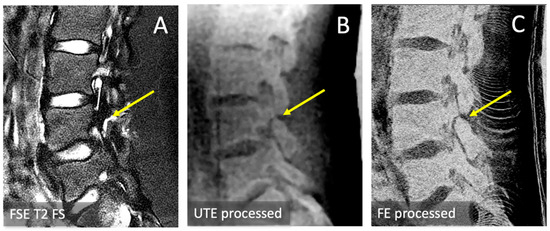

3.1. Observations

3.3. Spondylolysis Depiction